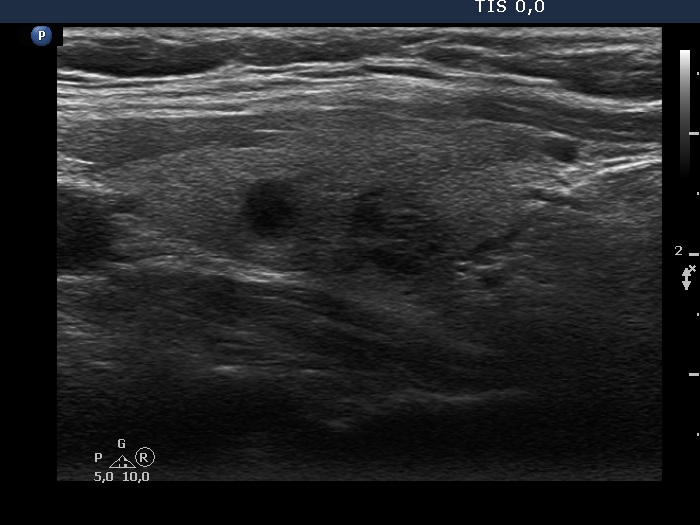

Intranodular hyperechogenic figures - case 372 (ultrasonographic picture 7)

Left lobe, longitudinal scan. Two lesions without any clinical significance are demonstrated.